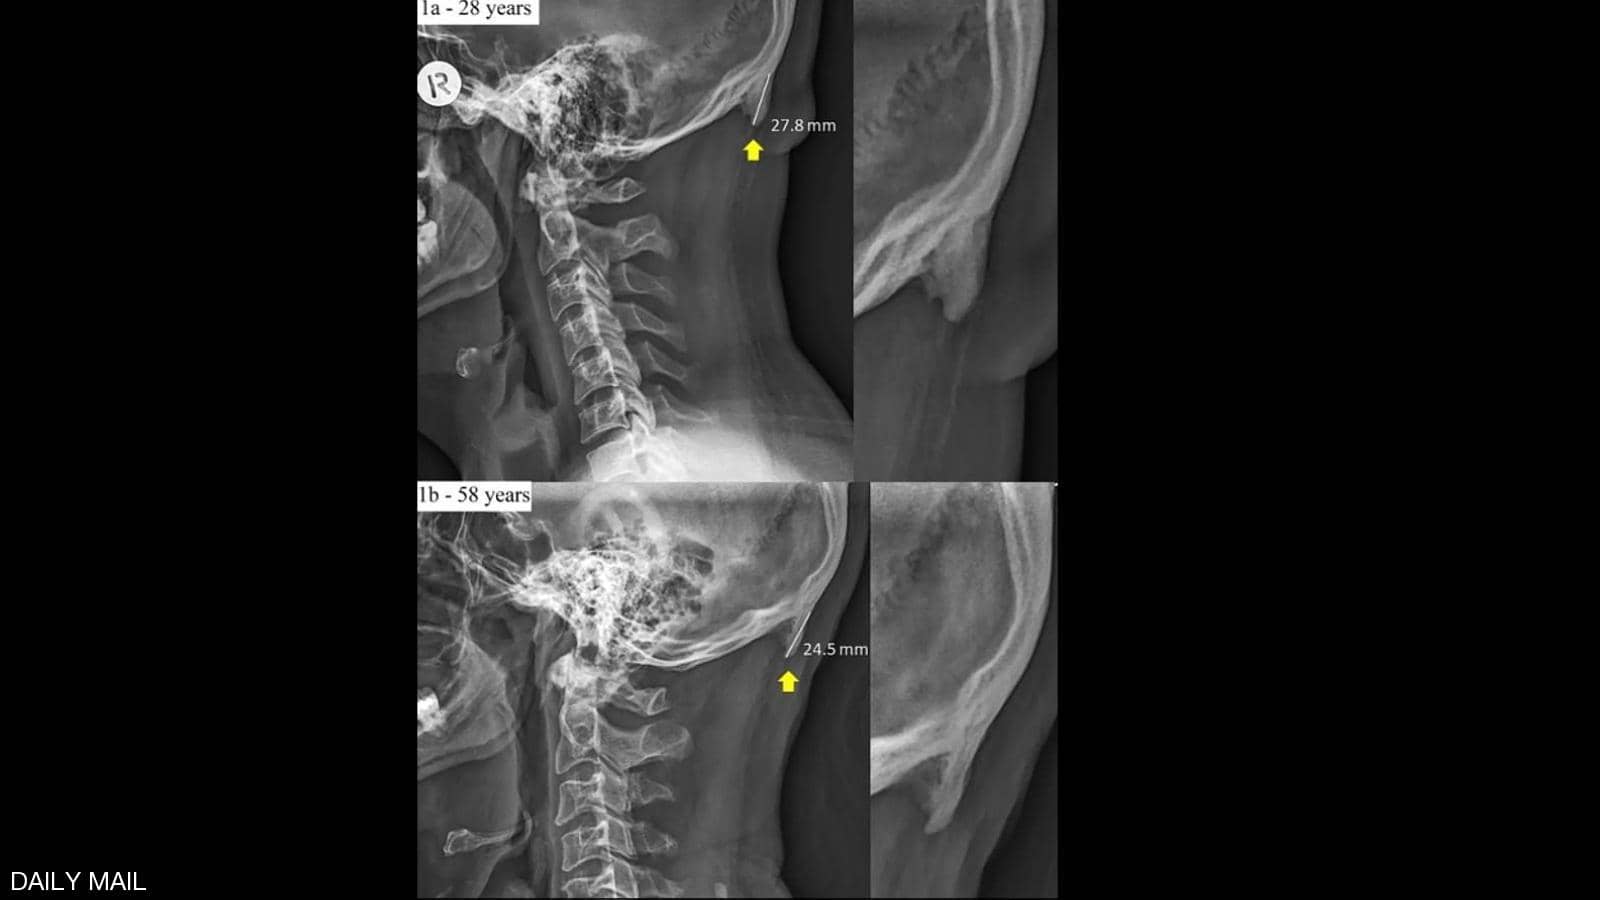

| دراسة تحذر مستخدمي الهواتف من "الشوكة الجمجمية " |

يخشى الناس في العادة أن تؤثر الهواتف والأجهزة الإلكترونية على صحة عيونهم، بالنظر للأشعة التي تنبعث منها، لاسيما في الظلام، لكن خبراء أستراليين حذروا من ضرر أكثر خطورة.وبحسب... |